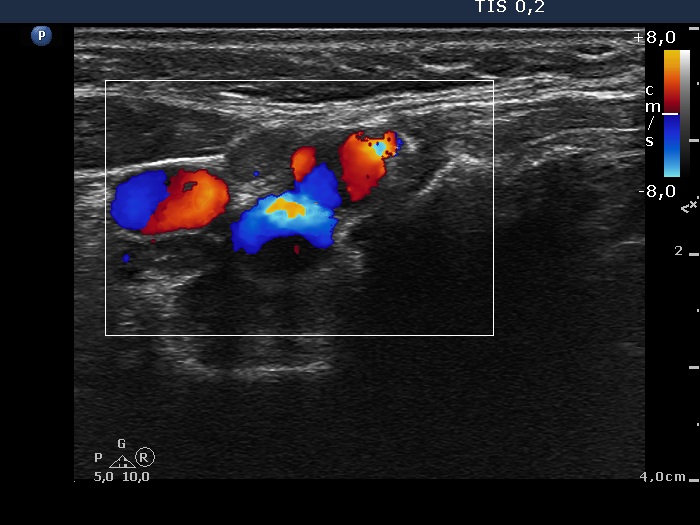

Lymph nodes in the neck - Case 674 (ultrasonographic picture 11)

Right submandibular area, transverse scan, color Doppler mode. There are two lymph nodes lateral and medial to the vessels, in the image left and right, respectively.